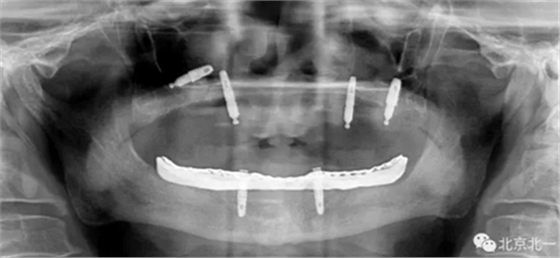

圖二:覆蓋義齒

圖三:植體負(fù)重一年后脫落掉入上頜竇,